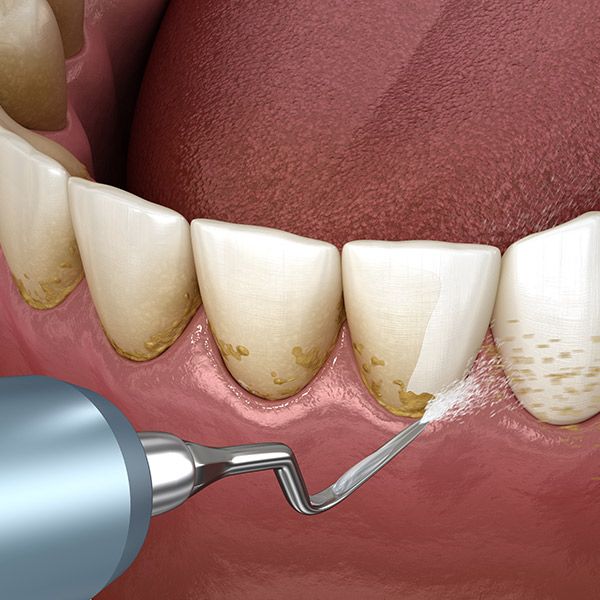

第一階段、牙周基本治療

1. 牙結石清除:一般俗稱「洗牙」,牙醫師會使用超音波洗牙機將牙結石震碎後洗除,過程不會損傷牙齒。建議一般人每半年進行一次口腔檢查及洗牙,不但可以定期清除牙結石,有效減少細菌量,預防牙周病,也可以及早發現蛀牙,及早進行治療。